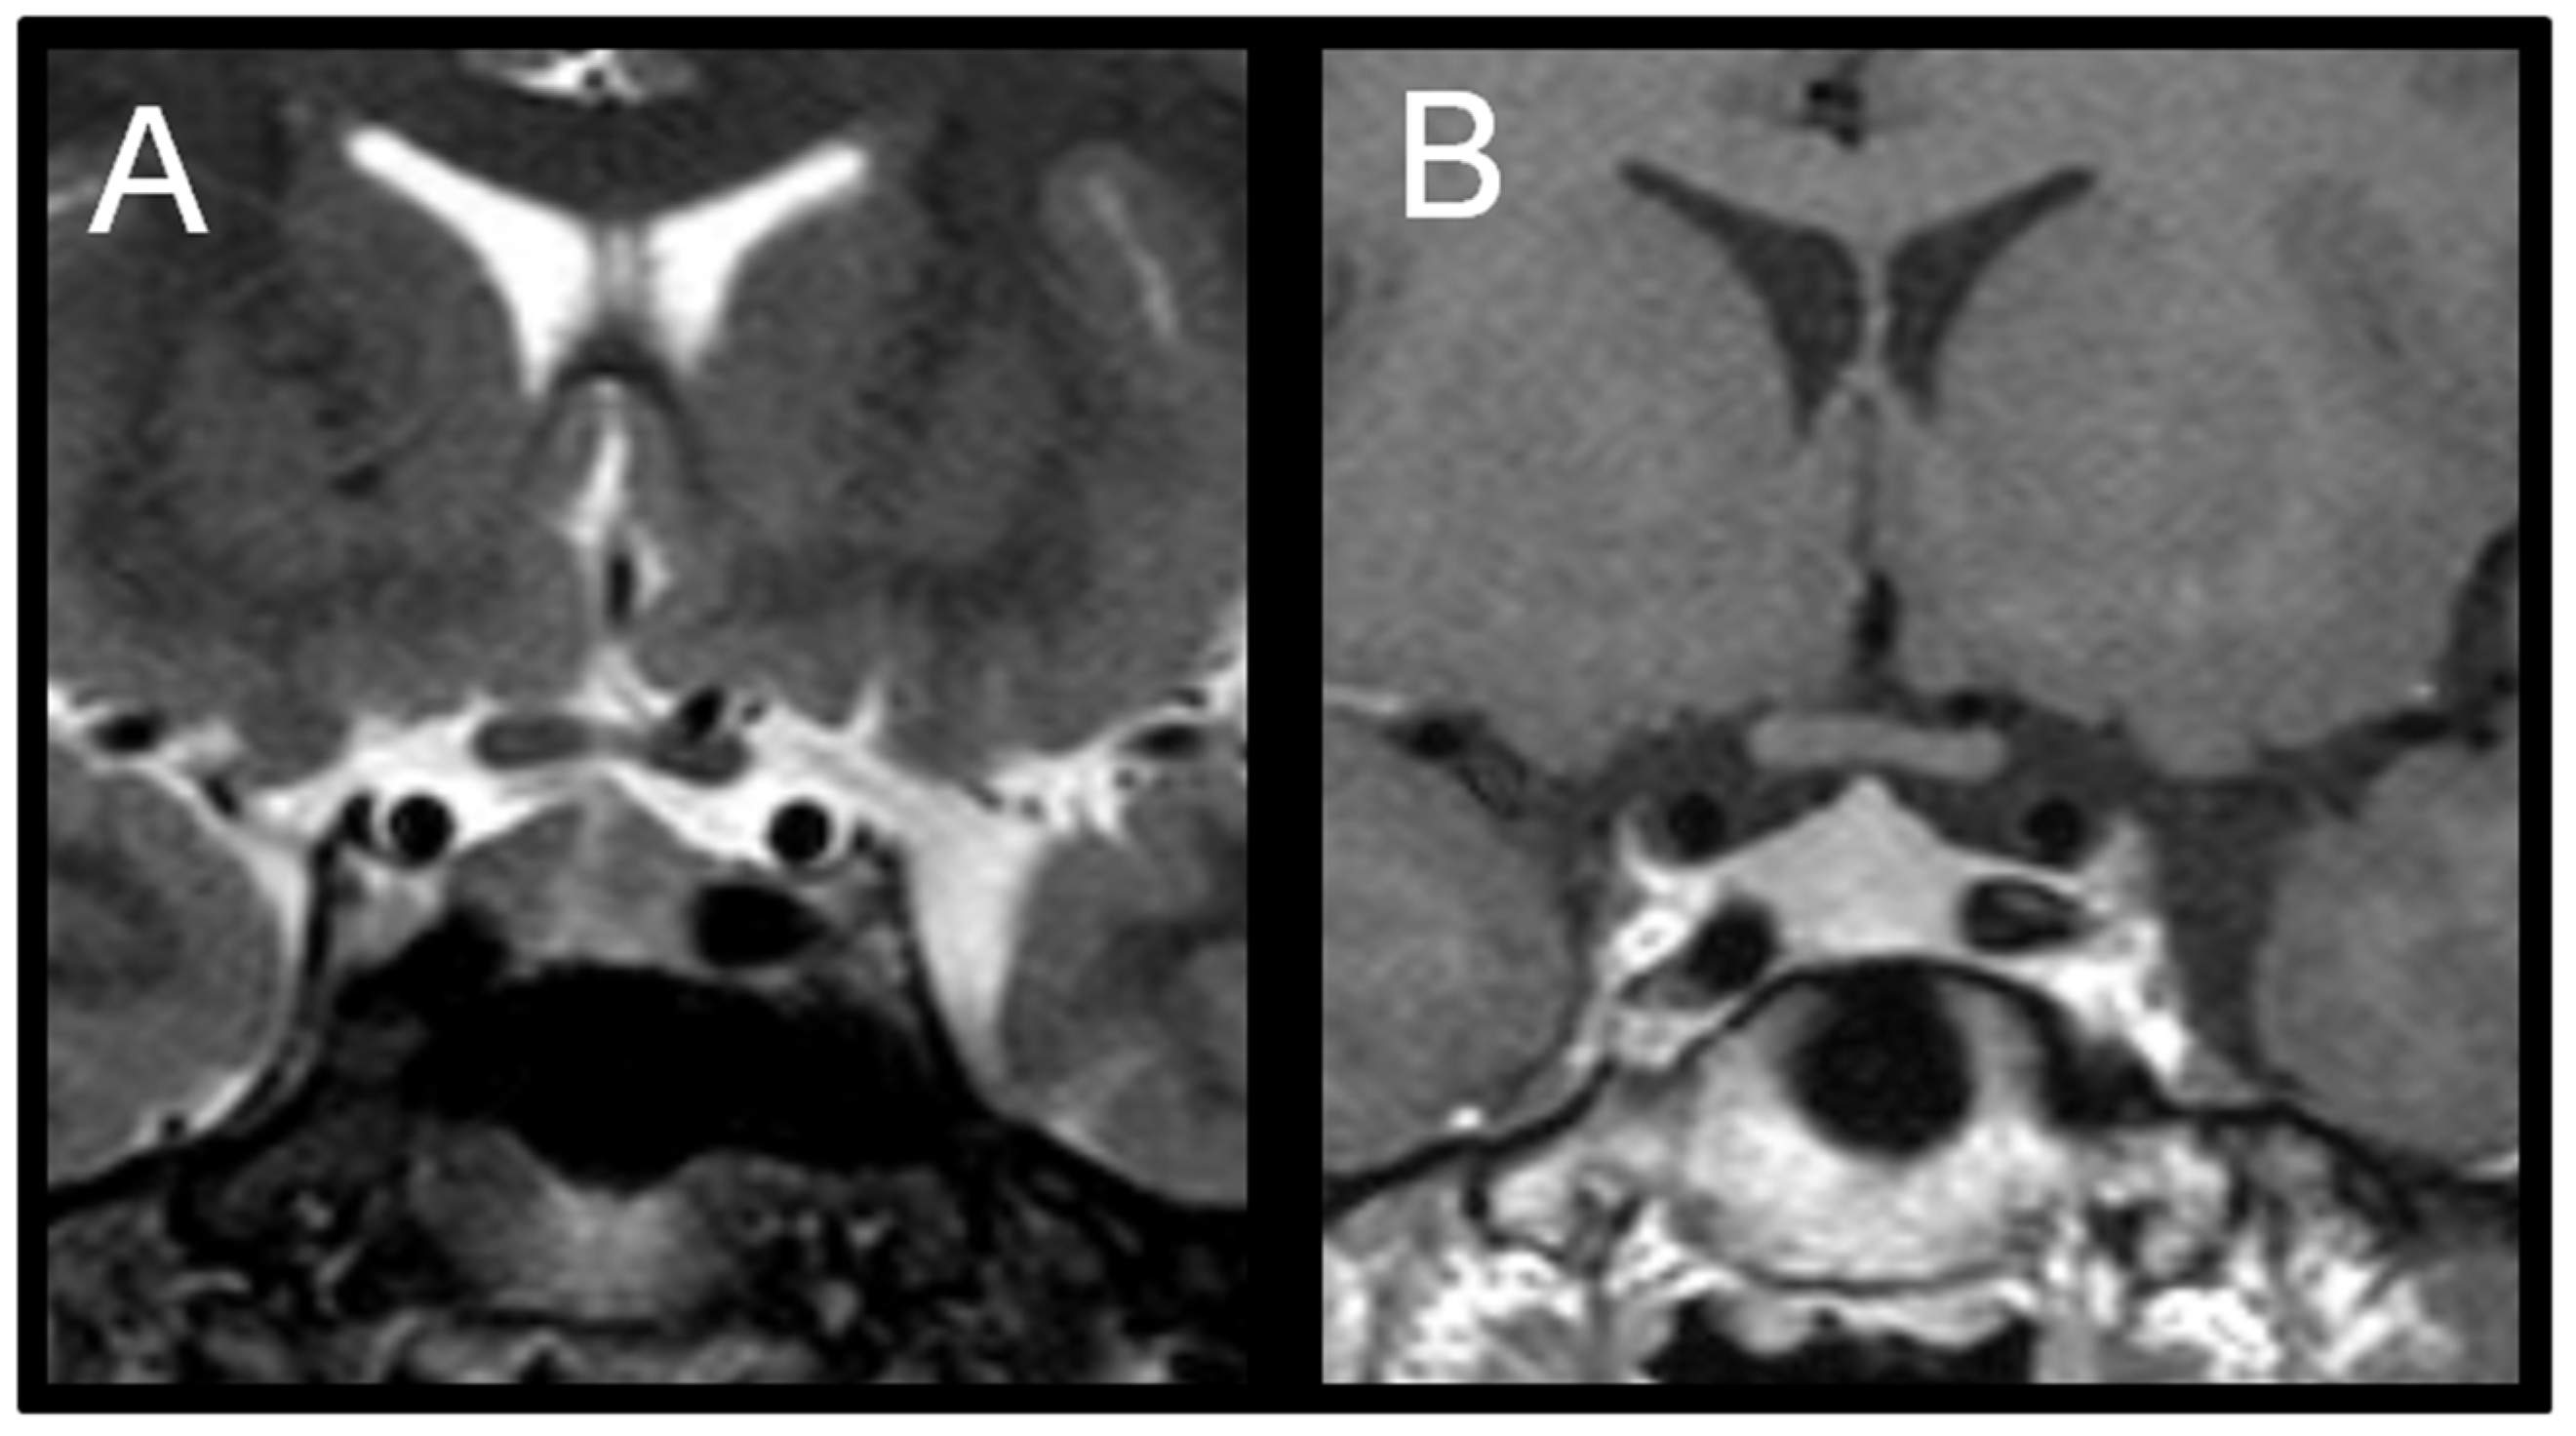

Because gonadotropins remained elevated, a pituitary MRI was repeated at the 24-month-follow-up (T24), which revealed an enlarged pituitary gland measuring 10 mm in height with superior convexity approaching suprasellar cistern, suggestive of reactive pituitary hyperplasia (Figure 2).

Figure 2.

(A) Coronal T2-weighted image shows symmetric enlargement of the pituitary gland. (B) Coronal T1-weighted post-contrast image shows homogeneous enhancement; maximum height of pituitary gland is about 10 mm.